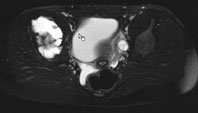

Die Röntgenuntersuchung von Becken/Hüfte zeigt eine septierte geographische Osteolyse in der Ala und im Korpus des Os Iliums rechts. Das Röntgenbild und die Aufnahmen der nachfolgenden MRI-Untersuchung sehen Sie hier: